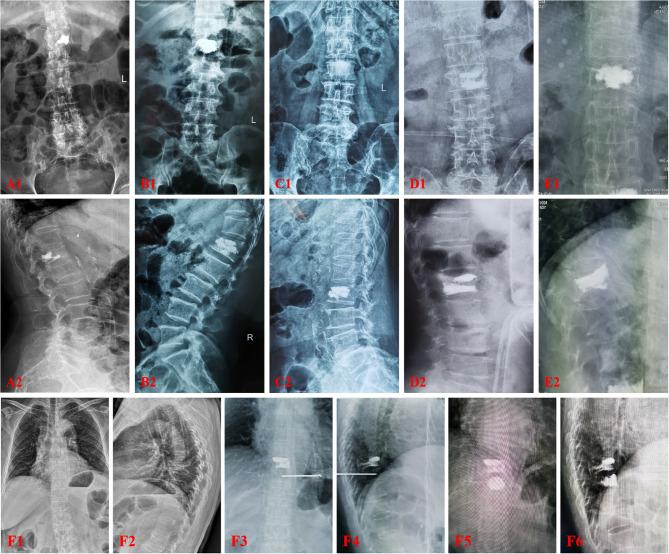

According to the inclusion criteria, 329 patients who underwent PVP in the Spinal Surgery Department of the Sixth Affiliated Hospital of Xinjiang Medical University between January 2018 and May 2024 were then retrospectively screened, and the patients were divided into two groups based on whether refracture occurred during the follow-up period. The two groups were (1) fracture group (n = 47) and (2) no fracture group (n = 282). The following variables were reviewed in both groups: age, gender, body mass index (BMI), PVP segment, cement leakage, bone density, T, cement dose, smoking, drinking, hypertension, type 2 diabetes mellitus, COPD, cerebral hemorrhage, coronary heart disease, cement DI type, chronic kidney history and previous fracture (caused by osteoporosis). These factors were univariate analyzed and replaced P < 0.05 with binary Logistic analysis to explore the factors associated with postoperative vertebral recompression fracture.

A total of 329 patients were included in this study to compare the parameters between the fracture and nonfracture groups. The results of univariate analysis showed that postoperative vertebral refracture was related to age, cement leakage, bone mineral density T value, history of hypertension, history of type 2 diabetes mellitus, the index type of bone cement distribution, and chronic kidney disease, and the difference was statistically significant (P < 0.05). By binary Logistic regression, Age (OR = 1.103, 95%CI:1.041-1.179, P = 0.002), leakage of bone cement (OR = 11.790,95%CI:4.942-30.637,P < 0.001) MD T value (OR = 5.716, 95%CI: 1.575-28.548, P = 0.016), history of hypertension (OR = 2.721, 95%CI:1.155-6.612, P = 0.023), history of chronic kidney disease (OR = 6.360, 95%CI:1.435-30.833, P = 0.017), type I bone cement DI [OR = 13.636, 95%CI: 3.126-98.477, P = 0.002] and type II cement DI [OR = 8.590, 95%CI:1.890-62.651, P = 0.012] was a risk factor for refracture of the operated and adjacent vertebrae.

The results showed that age, cement leakage, bone mineral density T value, history of hypertension, and cement DI type were risk factors for refracture of the operated vertebrae and adjacent vertebrae. The surgeon conducts a comprehensive evaluation of patients before surgery, which can more accurately estimate the probability of fracture again, and then provide a reference for the formulation of personalized treatment plan, so as to reduce the risk of fracture again in the future.